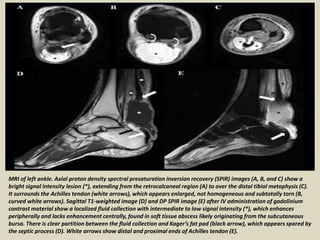

MRI of left ankle. Axial proton density spectral presaturation inversion recovery (SPIR) images (A, B, and C) show a

bright signal intensity lesion (*), extending from the retrocalcaneal region (A) to over the distal tibial metaphysis (C).

It surrounds the Achilles tendon (white arrows), which appears enlarged, not homogeneous and subtotally torn (B,

curved white arrows). Sagittal T1-weighted image (D) and DP SPIR image (E) after IV administration of gadolinium

contrast material show a localized fluid collection with intermediate to low signal intensity (*), which enhances

peripherally and lacks enhancement centrally, found in soft tissue abscess likely originating from the subcutaneous

bursa. There is clear partition between the fluid collection and Kager’s fat pad (black arrow), which appears spared by

the septic process (D). White arrows show distal and proximal ends of Achilles tendon (E).